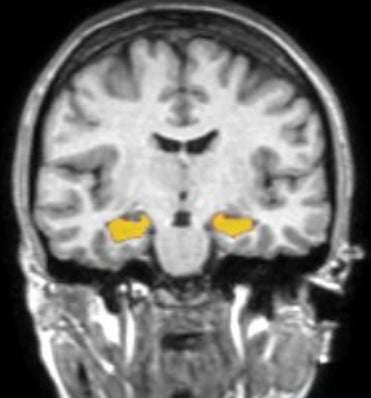

海馬とは?

海馬は、記憶をつかさどる脳の部位です。

記憶力や判断力等の低下は、海馬の萎縮として先に現れることが分かっています。加齢に加え、睡眠不足や運動不足など、生活習慣の乱れがその一因とされています。

しかし、6か月以上の運動をすることによって、海馬で「神経新生」が起こり、体積が増える可能性も示されています。

(PNAS, 2011, Erickson KI, Voss MW, Prakash RS, et al.)